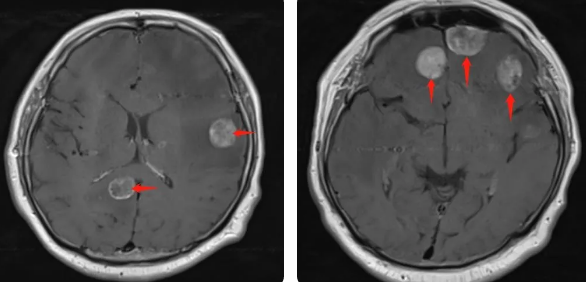

無獨(dú)有偶,60歲的左肺癌患者石先生,在外院接受了手術(shù)治療,結(jié)果術(shù)后10月出現(xiàn)腫瘤腦轉(zhuǎn)移,頭部增強(qiáng)MRI顯示:顱內(nèi)多發(fā)占位性病變伴水腫,接二連三的重?fù)糇屖壬霈F(xiàn)表情淡漠,沉默寡言,絕食等抑郁癥狀,VMAT放療技術(shù)與心理疏導(dǎo)雙管齊下,3周的治療后顱內(nèi)轉(zhuǎn)移病灶顯著縮小,部分甚至消失,困擾石先生的頭痛、頭暈癥狀也不復(fù)存在,石先生重拾對(duì)生活的希望,也對(duì)未來的治療充滿信心。